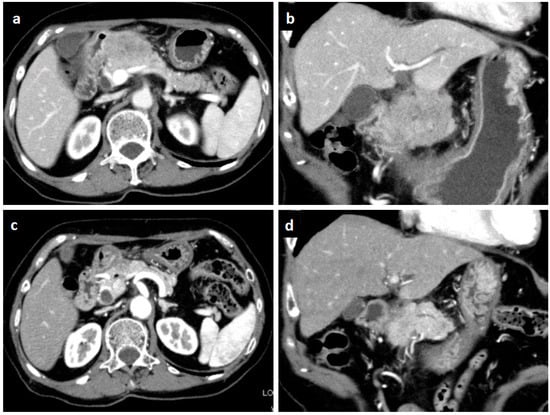

Figure 2.

Endoscopic view of the duodenal bulbs. A hemispheric submucosal tumor with apical erosion was recognized.